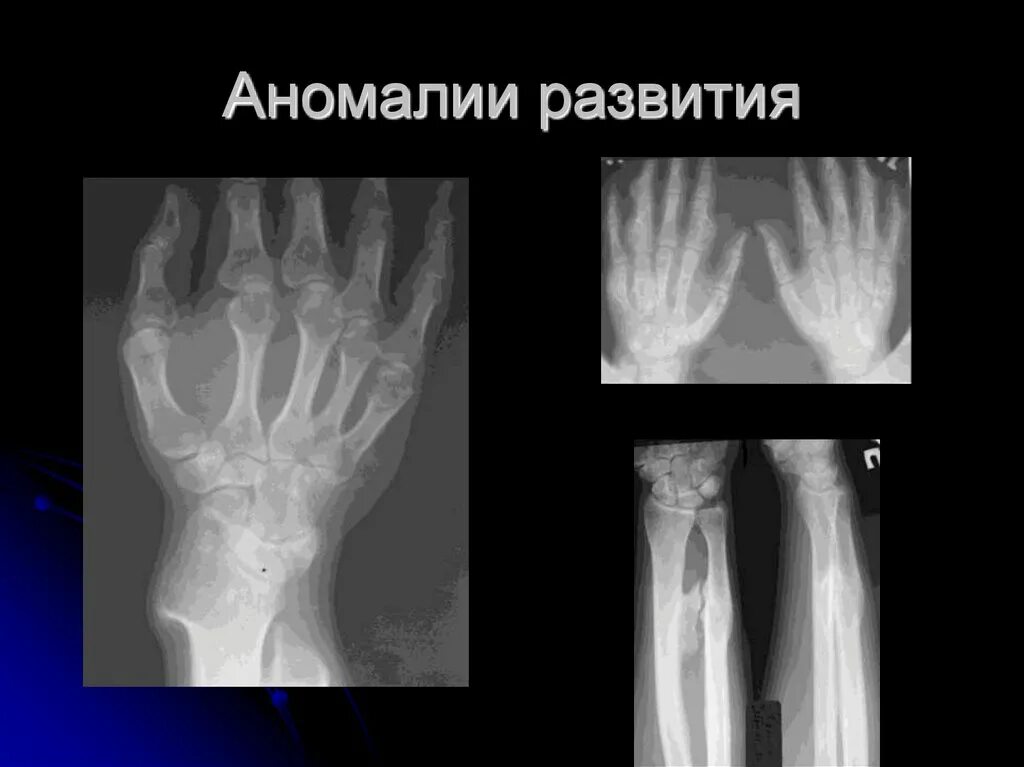

Аномалии костей